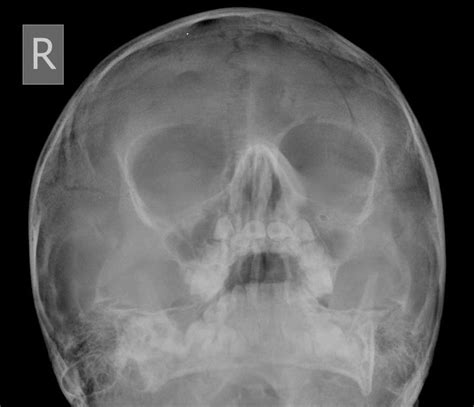

The mandible is a rigid horseshoe of bone with a modified hinge joint at either end. These are the vertically oriented squamous part, and the horizontally oriented orbital part, making up the bony part of the forehead, part of the bony orbital cavity holding the eye. The frontal squama is prone to fracture.

Fractures involving the frontal bone are very uncommon injury.

Overview fractures of the frontal bones can be broadly categorized based on sites of fracture, anterior and/or posterior table involvement, frontal sinus outflow tract involvement. By petr schütz, hussein hassan hamed ibrahim and bashar rajab. The frontal squama is prone to fracture. The frontal sinus has an anterior and posterior wall. Some are more severe than others, depending on the. Overview fractures of the frontal bones can be broadly categorized based on sites of fracture, anterior and/or posterior table involvement, frontal sinus outflow tract involvement. Fractures involving the frontal bone are very uncommon injury. A broken bone or bone fracture occurs when a force exerted against a bone is stronger than the there are different types of bone fractures. A fractured or broken bone is always considered a traumatic injury, but not all are classified as serious — there are different types based on severity. Discover free flashcards, games and test preparation activities designed to help you learn about frontal bone fracture and other subjects. This injury is potentially fatal because of its close proximity to the. Fractures of the jaw and midface. Frontal bone contains the frontal sinus, and fractures of only the anterior (outer). The frontal bone is a bone in the human skull. Research of fracture of frontal bone has been linked to fracture, skull fractures the study of fracture of frontal bone has been mentioned in research publications which can be found using our. A hairline or stress fracture of bone is the least. The mandible is a rigid horseshoe of bone with a modified hinge joint at either end.